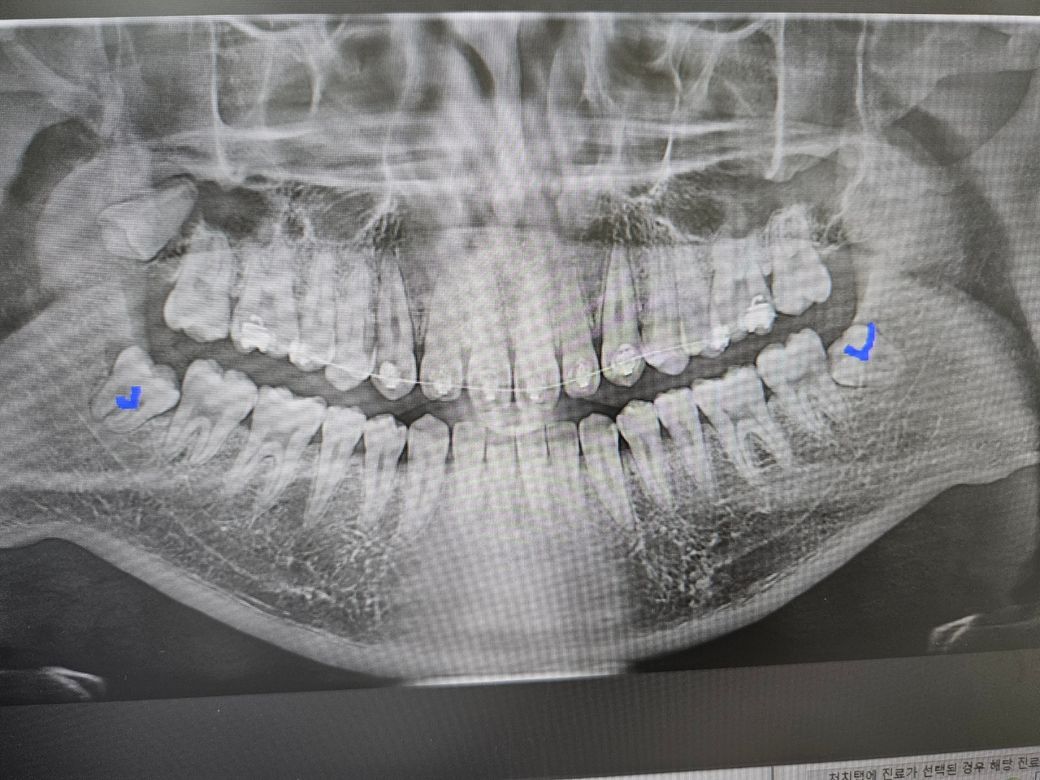

위에 매복 사랑니 하나를 뽑아야할까요?

밑에 사랑니는 뽑았구

위에 사랑니 하나 남은 상태입니다.

겉으로 확인했을때는 매복이고 딱하 아프거나 그런것도 없습니다.

뽑지않아도 상관없는 사랑니 일까요?

개인적으로는 매복이기도하고 생긴게 뽑기 힘들어보여서 뽑지않아도 문제가 생기지않는다면

뽑지않고싶어요..

위쪽의 현재 매복사랑니의 경우 추후 문제를 일으킬 가능성이 높아보입니다.

그렇기 때문에 미리 발치를 하시는 것이 좋을 것 같습니다.